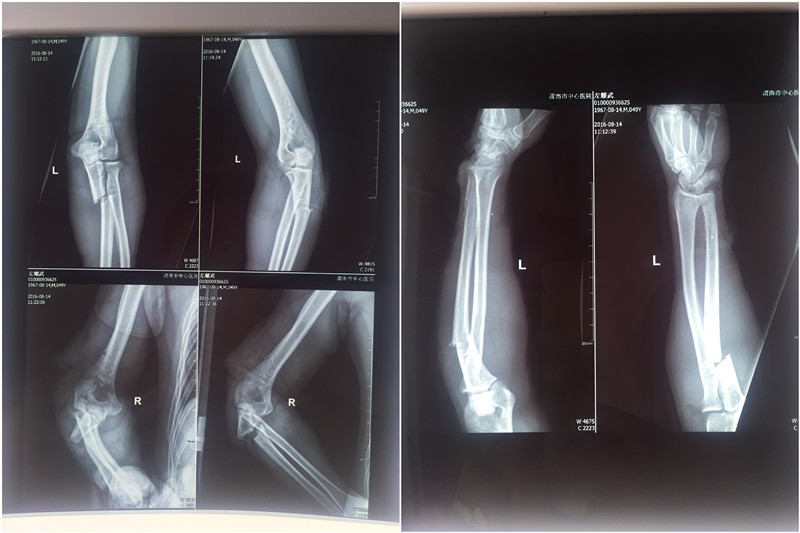

手术前

近日,一名中年男子左先生遭遇意外,被数人用刀砍伤双上肢及左下肢,立即被120送往我院急诊科,骨一科接到急诊科会诊电话后迅速对左先生进行紧急抢救。经过快速输液、拍片等检查,随即转往骨一科进一步治疗。初步诊断为:双侧尺骨多处开放性骨折、桡骨开放性骨折、右侧肱骨开放性骨折、桡神经丶尺神经、肌皮神经断裂、全身多处肌肉、肌腱断裂。